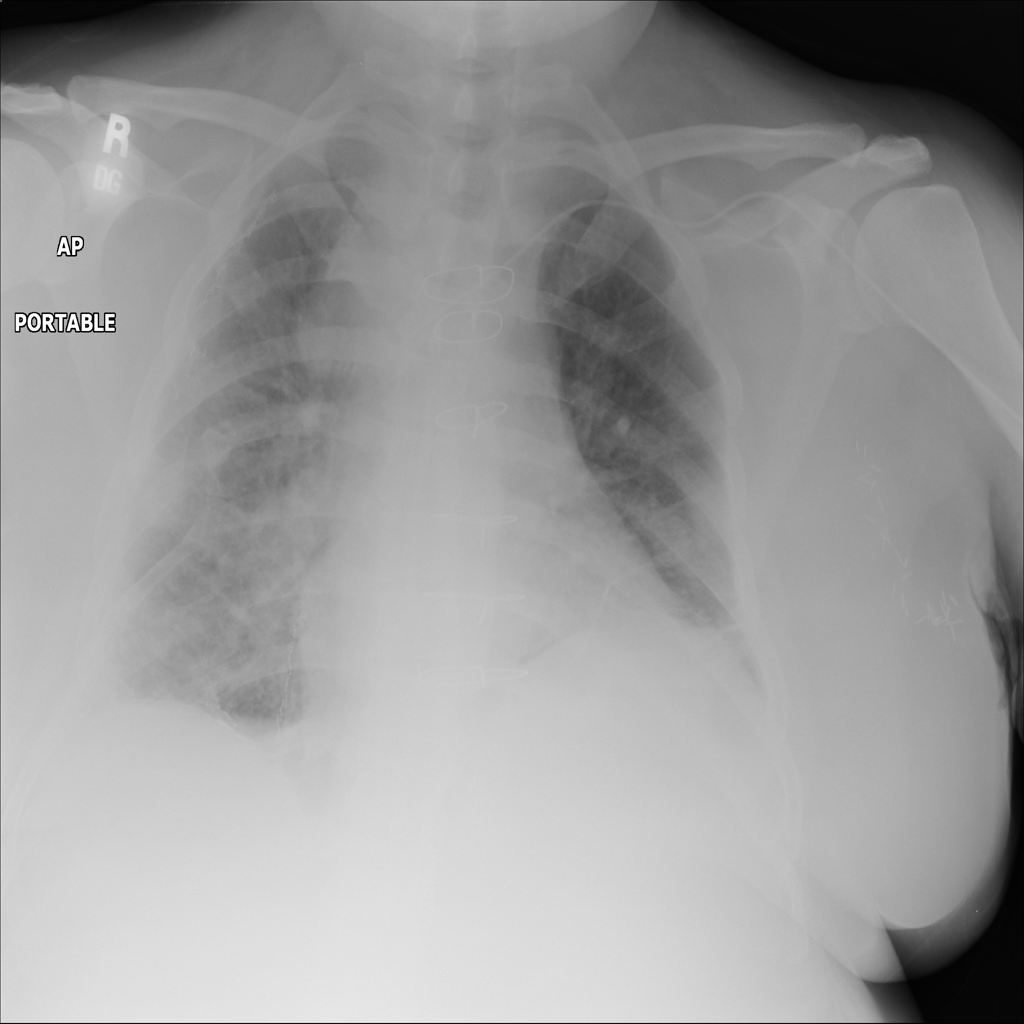

AP

PAT-595E · IMG-009Atelectasis

PAT-595E · IMG-009